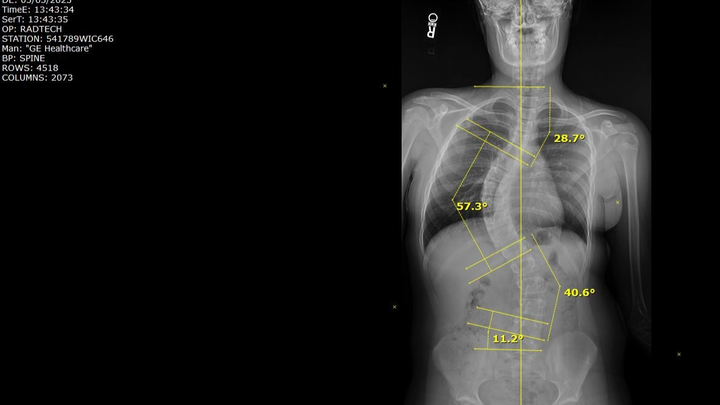

Her journey began just 2 months into her time on Earth with us. She was diagnosed with Cystic Fibrosis, and through her maintenance around that disease, we discovered the curvature in Azalya’s spine. At the time, we were told to just wait and see... little did we know, that is the last thing you want to do with a curve in your back while still growing. By the time she was seen again, her curve had significantly worsened, and we were referred to a specialist.

Last winter, we saw the specialist and were told there was nothing that could be done to reverse a scoliosis curve — and not to believe anyone who says otherwise. We were told she would need back surgery. We were determined to get a second opinion, and through some recommendations, we found the Scoliosis Care Center in San Jose.

After our initial inquiry and their team reviewing Azalya’s x-rays, things moved quickly. Due to the significance of her curvature and her age, we were urged to start treatments immediately. That meant school, dance, soccer, and Spring Break would have to wait. Two weeks later, we were in San Jose beginning our journey.